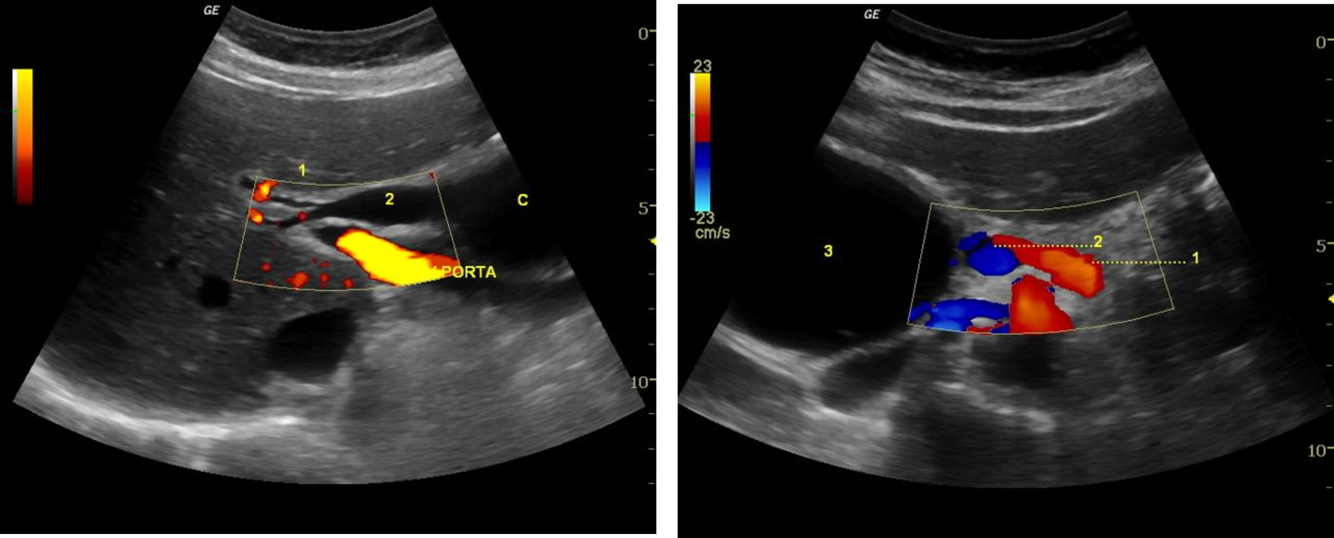

Ultrasound study shows a cystic mass between the pancreatic head and the gallbladder. Smooth wall and homogeneous anechoic content were detected.

The study is compatible with dilatation of entire extrahepatic bile duct, that’s also known as a true choledochal cyst. Is the type 1 of Todani classification of bile duct cysts.